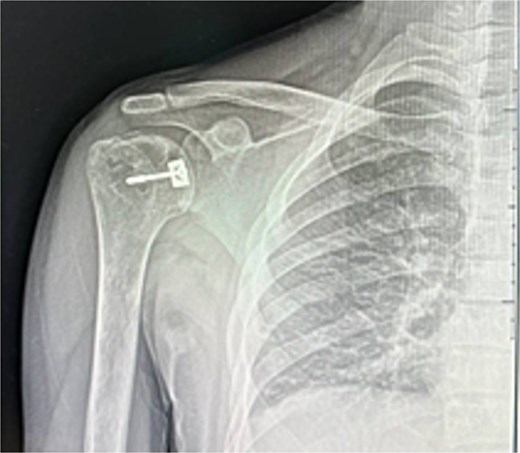

A 31-year-old male with sickle cell disease presented to the emergency department after an electrical shock caused him to fall onto the back of his shoulder. He developed severe pain and inability to use his arm. Examination revealed the shoulder in adduction and internal rotation with marked limitation of flexion and external rotation. X-rays showed posterior shoulder dislocation with a non-displaced proximal humerus fracture (Fig. 1). The injury was overlooked, and he was discharged in an arm sling.